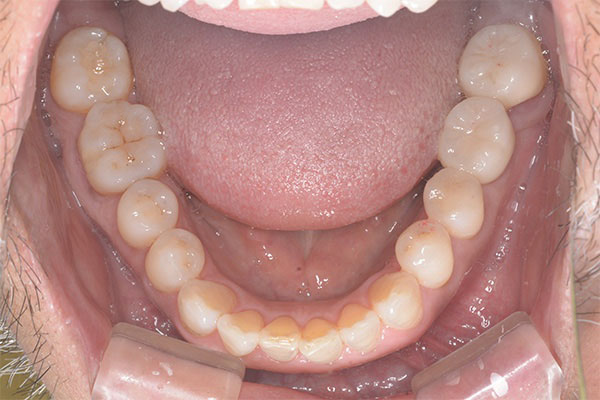

患者様の要望下の前歯の傾きを治したい

治療期間3ヶ月

治療費用275,000円(税込)

治療内容ワイヤー部分矯正

治療のリスク動的治療後、保定装置を決められた期間確実に装着しない場合に後戻りが起こる可能性あり